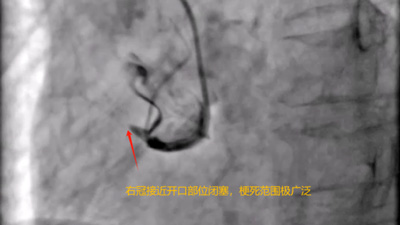

李某,88岁,女性,常驻宣恩县李家河乡二虎寨,因突发胸腹部疼痛,伴全身大汗,家属立马送往宣恩县李家河卫生院,急诊考虑急性心肌梗死,情况十分危急,冯尚波主任立马联系宣恩县人民医院胸痛中心,宣恩县人民医院徐昌金主任指示:急性下壁心肌梗塞,立即心梗一包药。

患者抵达来凤县人民医院后,取得家属同意立即被送入导管室进行手术。在心血管内科朱兴彪主任团队的协作下,凭借丰富的经验和精湛的技术,成功为患者开通闭塞血管,术后患者生命体征逐渐平稳,成功脱离生命危险。